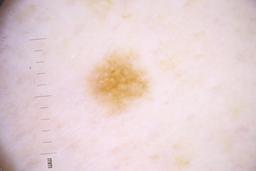

- Name: Challenge 2020: Training

- Number of images: 33,126

- Number of specified lesions: 32,701

- Number of specified patients: 2,056